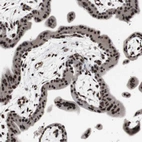

Immunohistochemical staining of human cerebral cortex shows strong nuclear positivity in neurons.